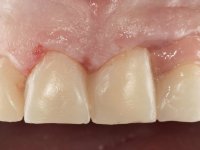

This addition of resin would guide the ceramist in the final placement of the gingival tonality ceramic. The crown that would rehabilitate tooth 1.3 was cemented in this test session with glass ionomer cement, reinforced with composite resin. Once the laboratory work was finished on the veneer for tooth 1.2, the abutment, and the veneer for the implant, this was bonded in the mouth, after placement of the absolute insulation. The work completely satisfied the patient. For eight years, the patient had periodical check-ups, and was pleased with the treatment, but also began to show interest in an aesthetical intervention on the upper central incisors. Once the second phase of our intervention was decided, dental preparation of teeth 1.1 and 2.1 was performed for the placement of two feldspathic veneers. Particular care was taken in the distal inter-proximal preparation adjacent to the abutment of the implant.

The axis of insertion of the veneer in relation to the abutment was very carefully evaluated. The feldspathic veneers were prepared in the laboratory and then bonded to the mouth after placing absolute insulation. One year later, we began our third phase of treatment, after the veneer in tooth 2.1 fractured. A dental preparation was done on the bonded veneer, seeking to extend the distal inter-proximal interface more to the palate. The objective would be to move the veneer to a more palatine contact point. Preparation of tooth 1.2 was limited to creating an insertion axis. After preparation, the total crown and laboratory veneer were bonded to the mouth. First, the crown was bonded using a relative insulation with Teflon, later the veneer was bonded after the absolute insulation placement. In the crown, I used this type of insulation to avoid the use of staples. It would be difficult to apply due to the shape and size of the tooth, and would also be aggressive to the soft tissues. After bonding procedures, the occlusal integration of the work was evaluated.